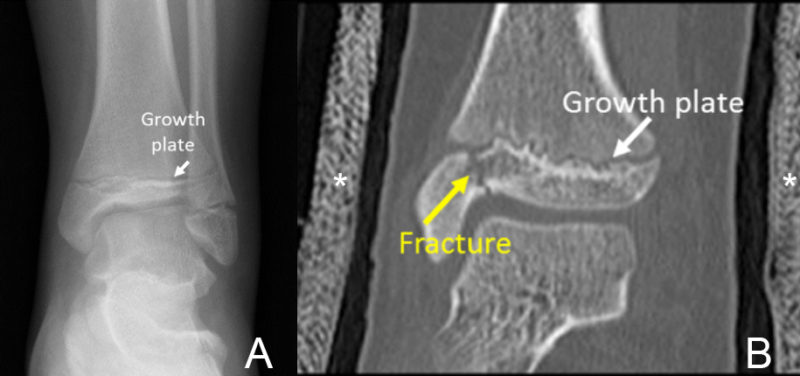

There are many ways to evaluate the injured ankle in a child. Most often, the imaging evaluation begins with x-rays. This is a quick and relatively inexpensive method, and most often is all that is needed to make a diagnosis. However, radiographs can occasionally miss fractures as the images are two-dimensional; there can also be overlap of structures. Details of fractures or visualization of how extensive a fracture is can be challenging, particularly if the fracture is complex and extensive.

In cases where more information is needed, computed tomography (CT) can be very helpful to evaluate fractures. CT offers excellent anatomic detail and can show how displaced a fracture is or if it involves a joint. Two- and three-dimensional representations also can be made, which can be helpful for diagnosis. CT is more expensive and does require more radiation than radiographs. However, with the most updated scanners at Cincinnati Children’s, the radiation dose is kept very low. A CT scan also can be done with a cast in place with little effect on the images. Your doctor, usually an orthopedic surgeon or sports medicine physician, will take all these factors into account when ordering a CT scan for ankle injury.

Particularly at the ankle, it is important to make sure that the joint surfaces affected by fracture are smooth in order to prevent future arthritis and pain. Many fractures of the ankle are treated with casts, but a small number will need surgery to restore the normal anatomy. CT examinations can help the doctor plan the most appropriate treatment.

The radiograph (A) from a 12-year old girl who fell shows a normal growth plate. A fracture was suspected but barely visible. A CT scan was requested in order to better see the fracture. 2D (B) and 3D (C) images made from the CT scan taken with the ankle in a cast (asterisk) show the fracture line (yellow arrow) that goes to the ankle joint more easily. In this child, the joint surface is smooth and the fracture pieces are close together, so no surgery was necessary.